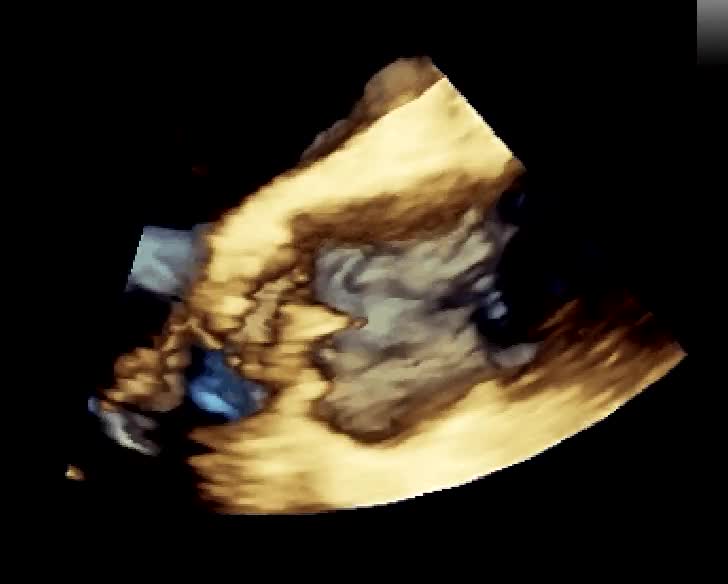

Insufficienza mitralica da rottura cordale